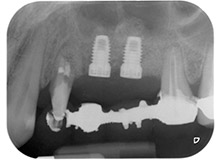

The implants (Restore, Keystone Dental, diameter 3,75 mm, length 8.0 mm) were placed with the implant motor

(Figs. 11 and 12).

Bone deficiencies around the implants, at the mesial aspect of tooth 27 and around the buccal root of tooth 24, were filled with xenogeneic bone substitute particles and covered with an absorbable collagen membrane (Bio-Gide, Geistlich Biomaterials) for GBR augmentation (Figs. 13 and 14).

Finally, after periosteal incision, the site was passively sutured with a coronally advanced flap, using 5-0 absorbable suture material (Fig. 15). The postoperative radiograph showed both implants in their correct vertical position (Fig. 16).